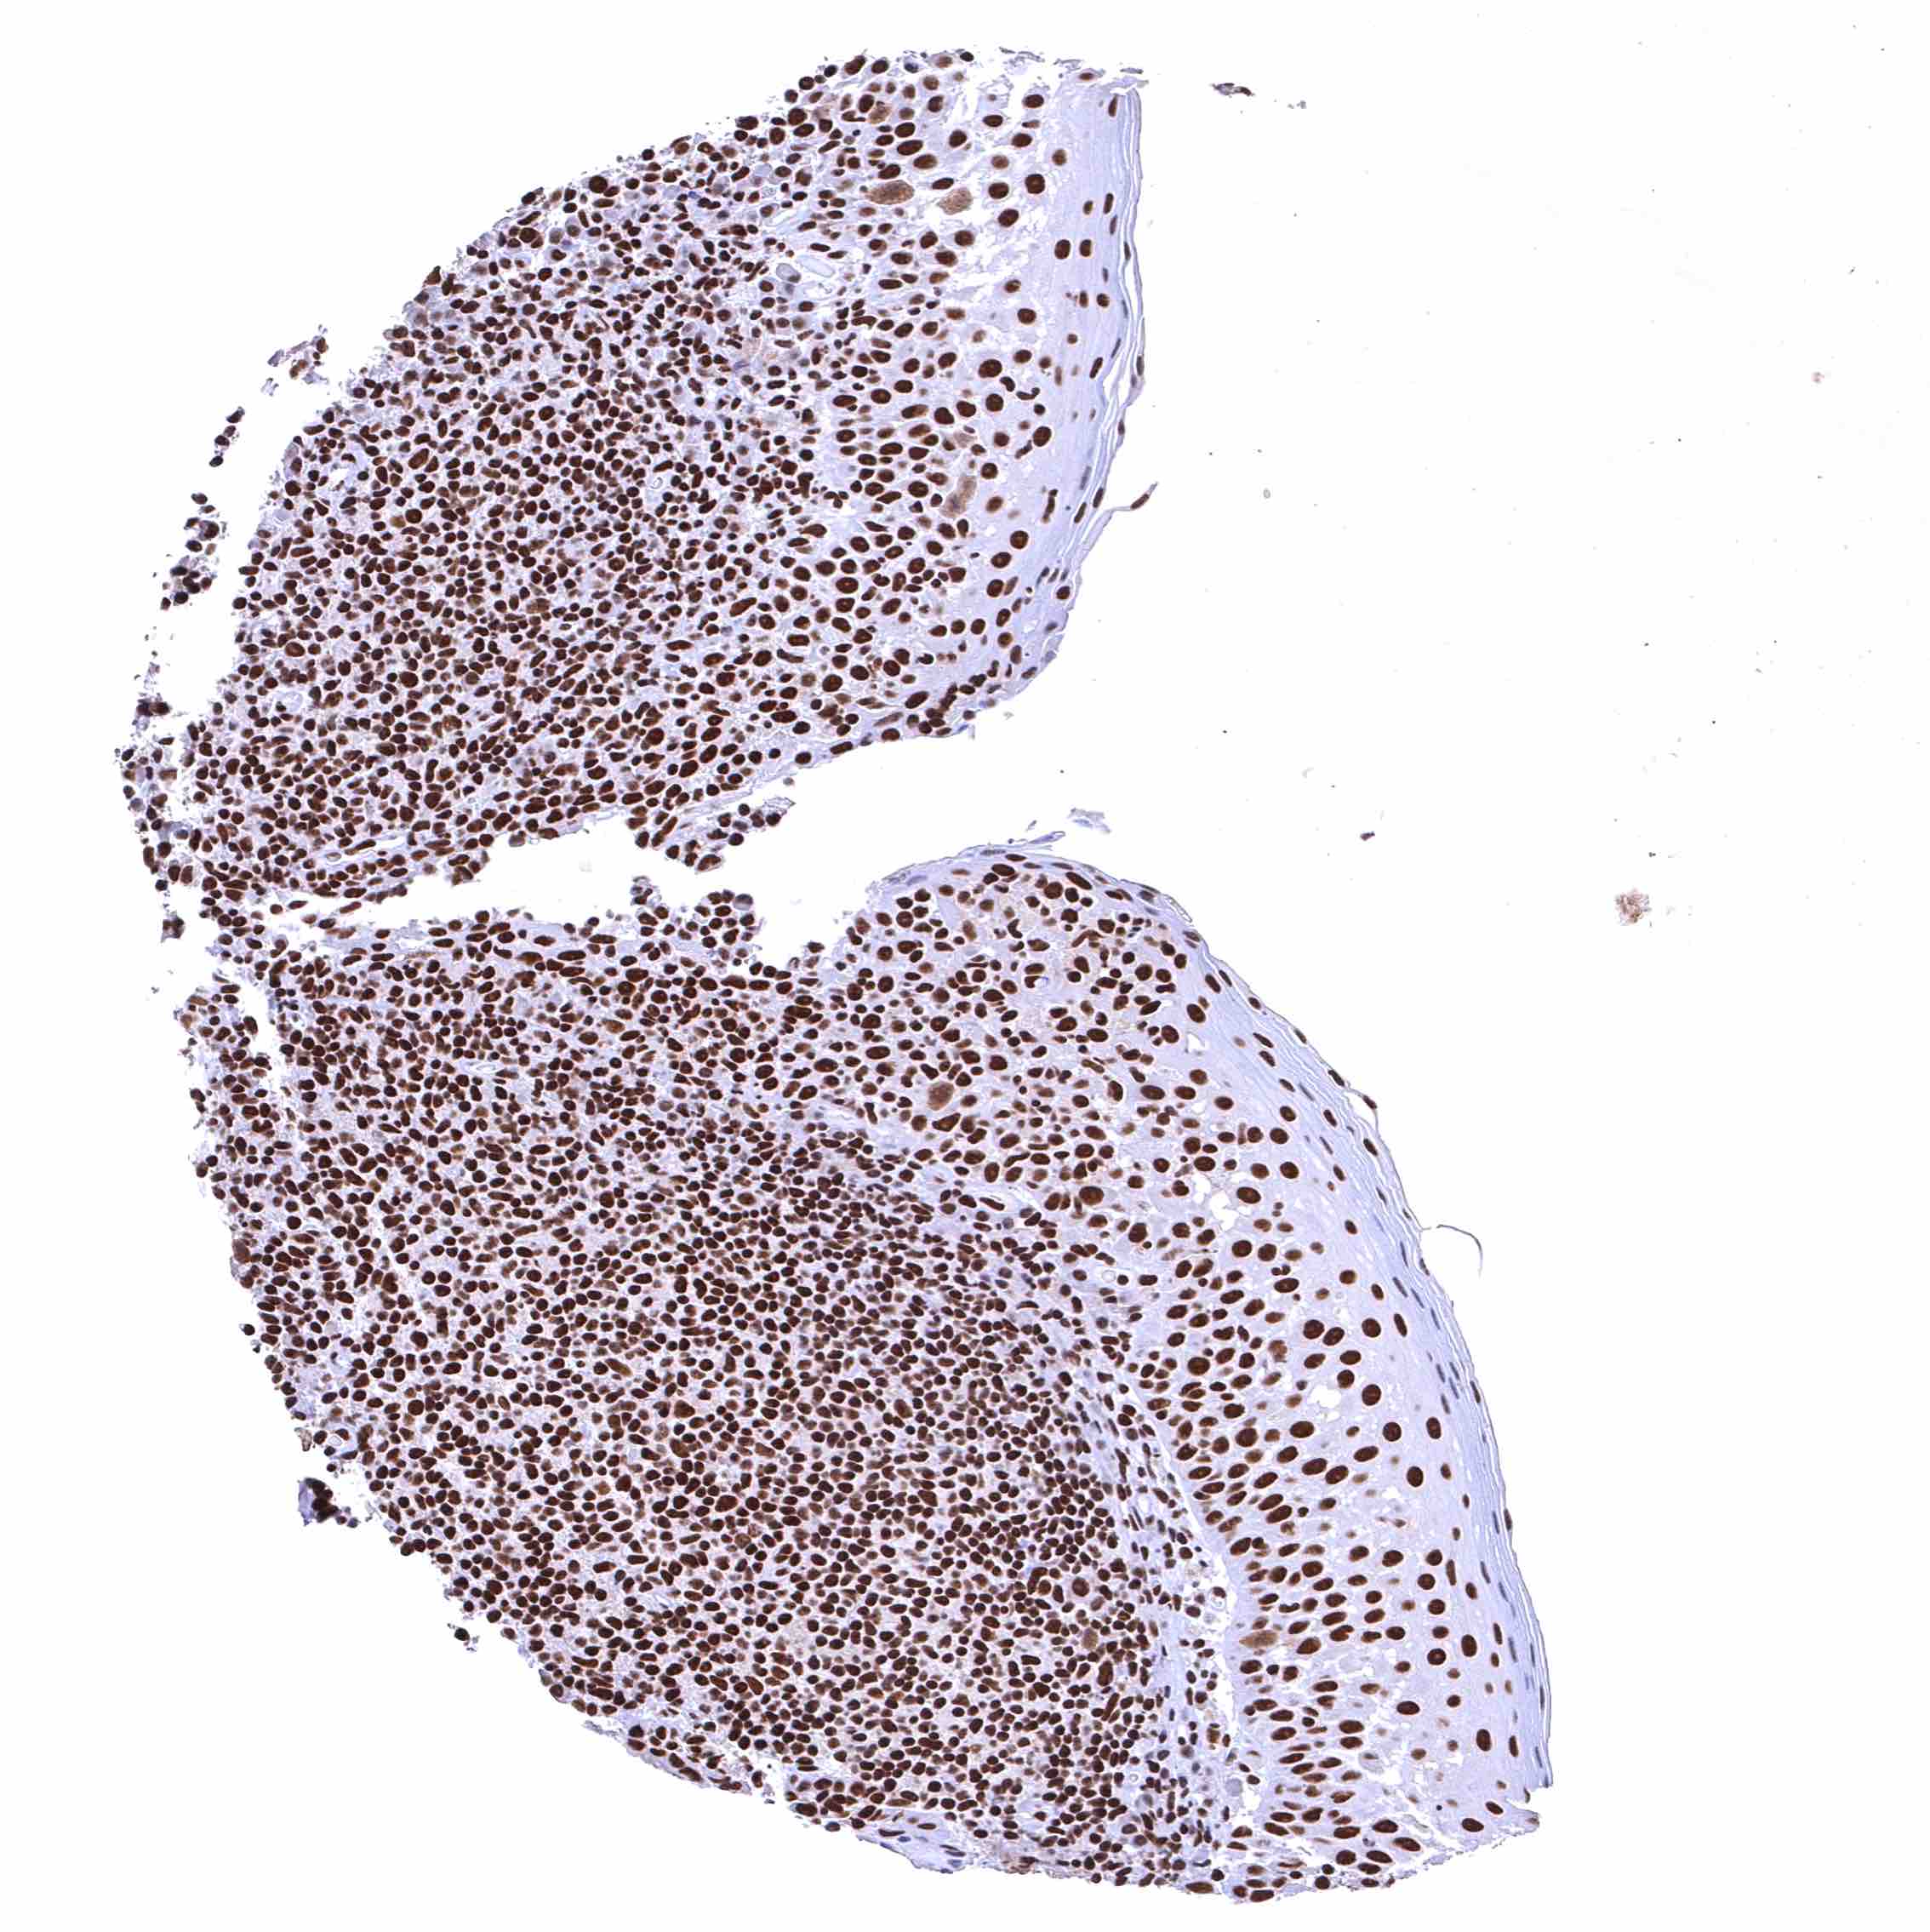

BRD4 antibody [HMV4275] HistoMAX™

Skin – Strong nuclear BRD4 staining of squamous epithelial cells.